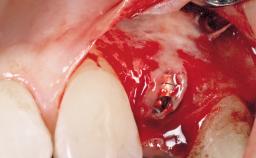

A 36-year-old female patient was referred for the replacement of the upper left central incisor (tooth 21), which had fractured. Although the tooth had been asymptomatic for many years, the crown began to loosen, at which time she presented to her dentist for an assessment. Teeth 21 and 22 had both been endodontically treated many years previously. She was a healthy individual and a non-smoker.

The crown of tooth 21 was splinted to the adjacent teeth with composite resin, and the gingiva was inflamed.

| Soft Tissue Grafting | Simultaneous |